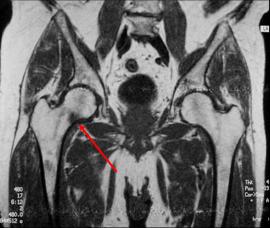

Insufficiency fracture

Occurs in the setting of underlying abnormal bone

Chronic hip soreness, patient with chronic renal failure